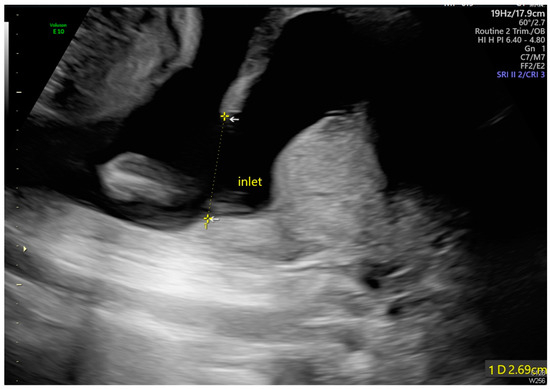

Intrauterine Adhesion-Induced Septated Amniotic Cavity: Ultrasonographic Findings in Second and Third Trimesters

Huang, J.-T.; Chen, Y.-M.; Tsai, C.-C.; Cheng, H.-H.; Lai, Y.-J.; Lee, P.-F.; Hsu, T.-Y.; Huang, K.-L. Intrauterine Adhesion-Induced Septated Amniotic Cavity: Ultrasonographic Findings in Second and Third Trimesters. Diagnostics 2024, 14, 2826. https://doi.org/10.3390/diagnostics14242826